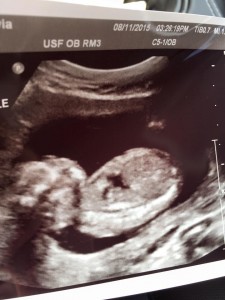

Evan and Olivia Rodriguez were excited to learn they were having a baby girl, whom they named Layla Sky. However, it was during that same ultrasound that they were devastated to hear something wasn’t developing correctly with their daughter.

“[The technician] was like, ‘I see something I don’t like. Her head is not completely round’, explains Mrs. Rodriguez. “They spent about an hour and half trying to figure out what was the problem.”

The couple learned that their precious baby girl has anencephaly, a condition in which the skull and brain don’t completely form. Baby Layla was otherwise healthy and active, so the couple went to another doctor for a second opinion.